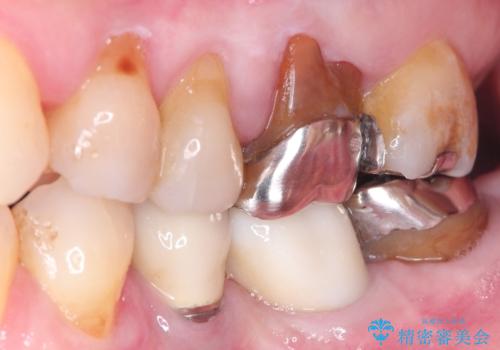

発見の難しい虫歯。根管治療から被せもの治療

- 定期検診にて被せものと歯との隙間に虫歯を発見した患者様です。

根管治療から被せもの治療(ベレッツァ)まで行いました。(根管治療は林院長に依頼)